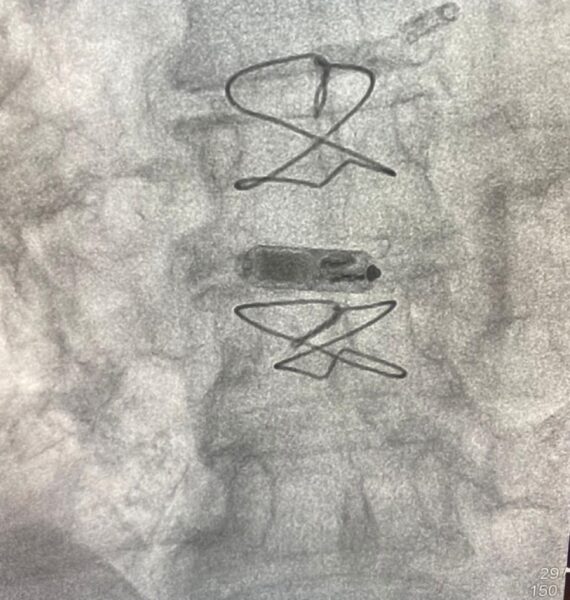

A implantação do pequeno marca-passo sem fios (eletrodos) ocorreu no Serviço de Hemodinâmica do Hospital Calixto Midlej Filho. O procedimento foi feito pela equipe comandada pelos médicos Gustavo Mendonça Duarte e Carlos Eduardo Duarte, e é inédito na Bahia, terceiro no Norte/Nordeste. Ele foi realizado pela primeira vez no Brasil em novembro de 2021. “No geral, o procedimento dura menos de uma hora e 24 horas depois o paciente recebe alta”, explica o cardiologista Gustavo Duarte.

A paciente que recebeu o Micra (nome comercial do dispositivo), considerado o menor marca-passo do mundo, teve um câncer na mama direita tratado com quimioterapia e radioterapia, além de um acesso do lado esquerdo (cateter), que, com o passar do tempo, causa a obstrução das veias do tórax, onde desce o fio do marca-passo convencional, conforme o médico Gustavo Duarte. “A paciente tinha um bloqueio atrioventricular, com histórico de desmaios. Isso precisava de uma resolução rápida”, afirma o profissional.

O cardiologista relata que, como as veias do tórax estavam todas obstruídas, a opção foi usar as veias da região da virilha para chegar até o coração. Depois o dispositivo sem fios foi implantado no coração para a estimulação do órgão. “Com isso, resolvemos um problema cardíaco sério que ela enfrentava”. Como o procedimento é menos invasivo e o marca-passo não tem fios, o risco de infecção depois do procedimento é menor.

Já o menor marca-passo do mundo é implantado diretamente no coração para correção de batimento e fica preso por quatro pequenas garras que possui. O Micra é produzido pela empresa Medtronic. O procedimento foi coberto por um plano de saúde. Como é muito caro, o serviço ainda não foi disponibilizado pelo Sistema Único de Saúde (SUS).